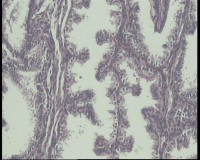

| 图片: | |

- 急!请老师看看34岁子宫内膜

| 性别 | 女 | 年龄 | 34岁 | 临床诊断 | 子宫内膜息肉? |

| 一般病史 | 末次月经:11月20日,近两个月无诱因性生活有阴道少许血性分泌物 | ||||

| 标本名称 | 宫内容物 | ||||

| 大体所见 | 膜样碎组织3.0厘米 | ||||